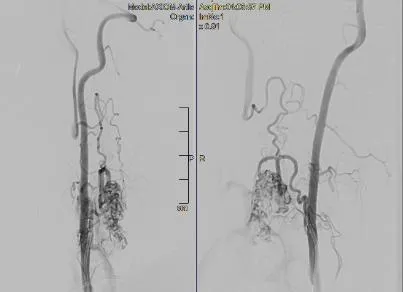

Hình chụp cho thấy anh Đ. bị dị dạng mạch máu tủy. Ảnh: BVCC |

Tại đây, anh Đ. được các BS hội chẩn và xác định bị dị dạng mạch máu tủy cổ bẩm sinh rất nặng, phức tạp và nguy cơ cao. Do không thể phẫu thuật hở, các BS phải can thiệp bằng phương pháp nội mạch DSA (hệ thống chụp hình mạch máu mới bằng tia X để thấy rõ các thương tổn và bệnh lý mạch máu trước khi chỉ định can thiệp mạch – PV).

Theo TS-BS Cường, anh Đ. rơi vào trường hợp dị dạng mạch máu tủy cổ bẩm sinh rất phức tạp. Do bệnh tiến triển trong một thời gian dài nên khối dị dạng quá to, chèn ép tủy lành gây yếu liệt tứ chi.